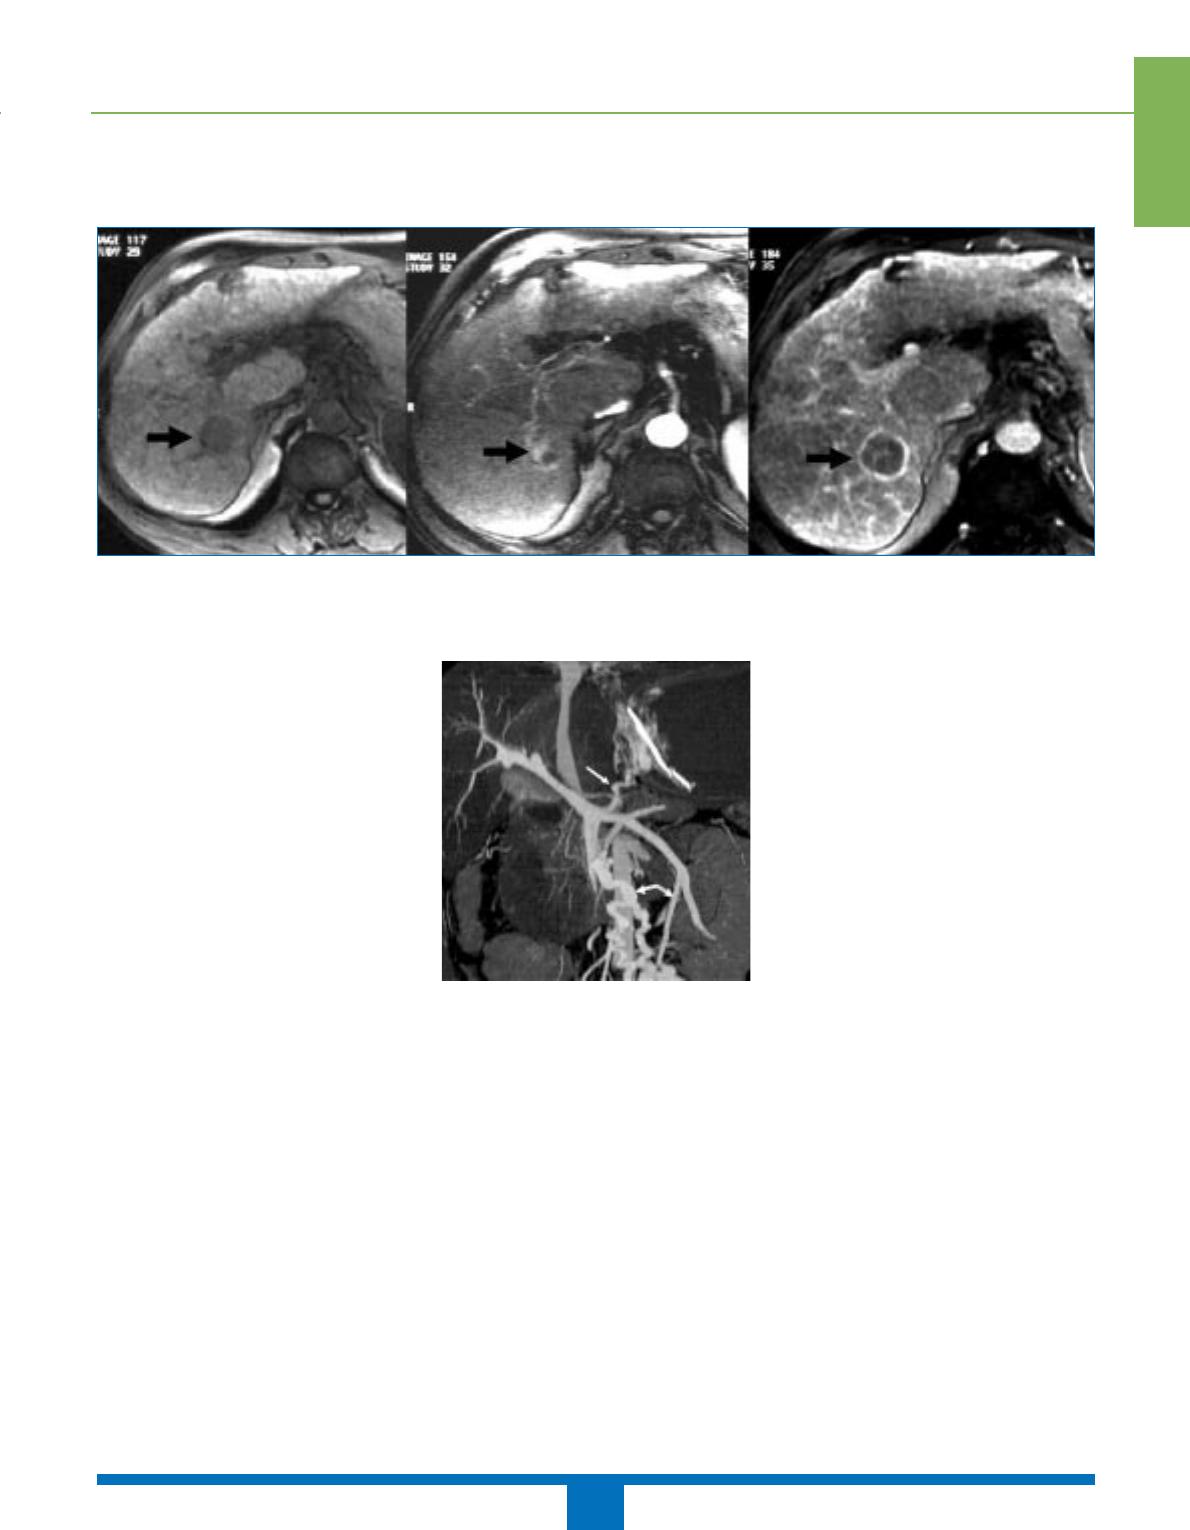

Les reconstructions MIP et VRT per-

mettent ainsi de visualiser préférentiel-

lement les vaisseaux par rapport aux

structures tissulaires adjacentes, don-

nant des images qui se rapprochent de

celles obtenues en artériographie.

Figure 2. Reconstruction en technique VRT

à partir de coupes scanographiques mon-

trant la vascularisation artérielle du foie

chez un donneur vivant avant prélèvement.